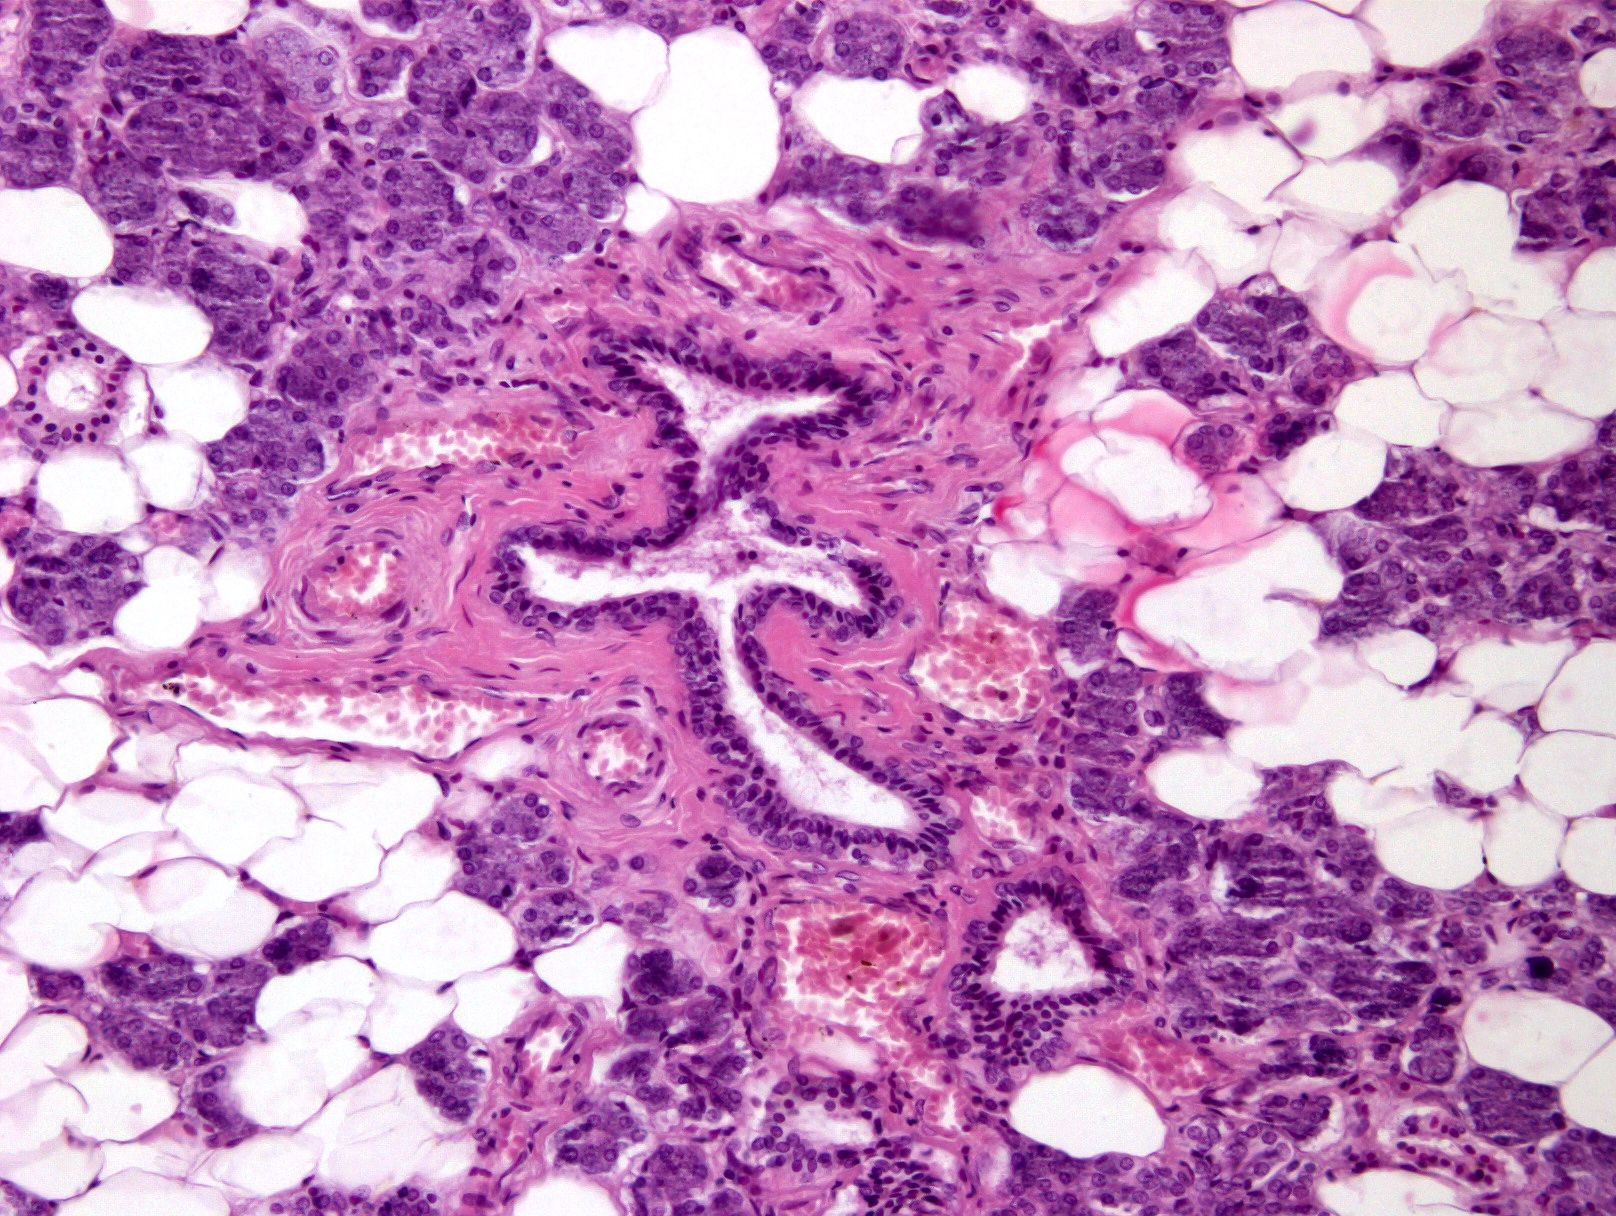

Match the micrographs with the organs - step 4

Match the micrographs with the organs - step 5

Match the micrographs with the organs - step 3

Match the micrographs with the organs - step 2